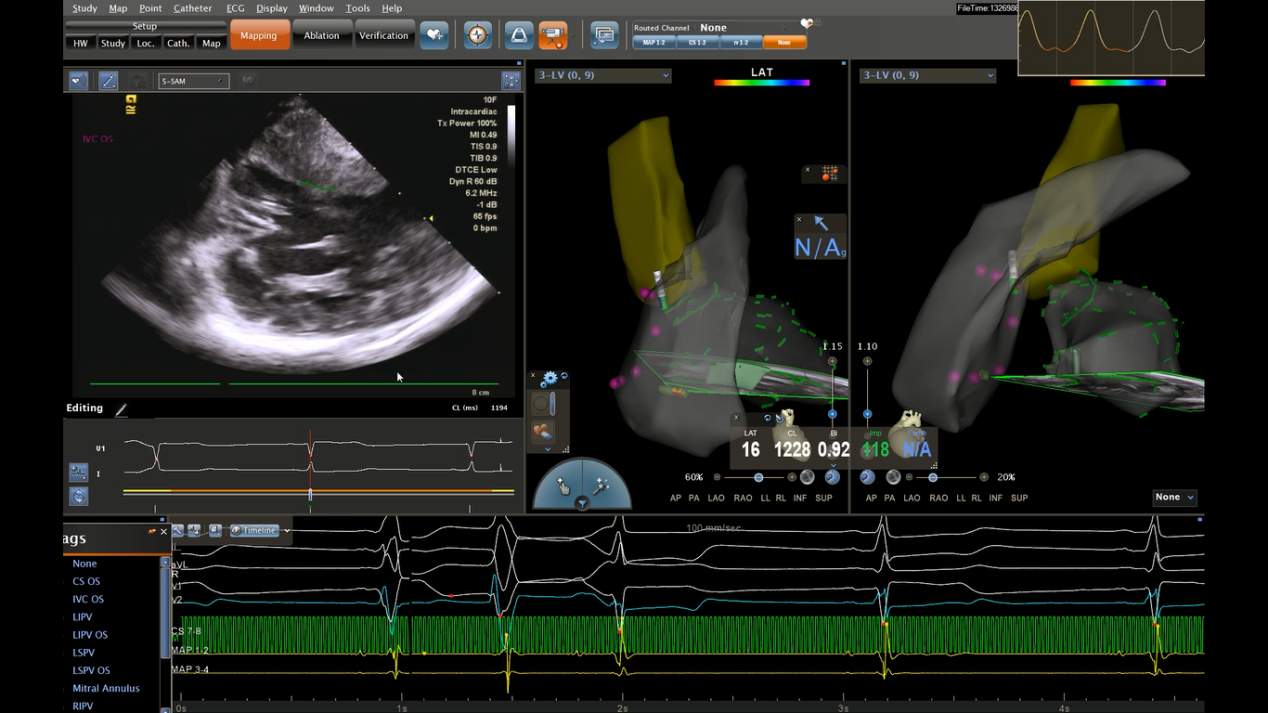

Carto三维构建左室模型:左图为超声定位下室间隔模型